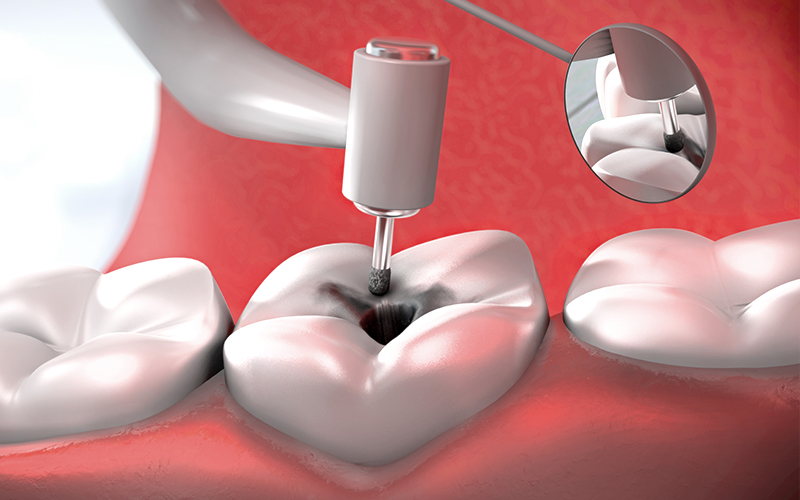

신경치료 과정

01

01

충치

02

02

충치제거